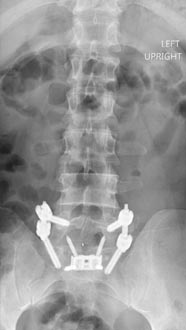

73 year old woman with osteoporosis who fell and fractured her pelvis. She was unable to walk and developed lumbopelvic dissociation (seperation of the spine from the pelvis and lower half of the body) from an unstable sacral fracture and displacement.

Lumbopelvic fixation with prophylactic cement augmentation and patient was immediately able to walk again.